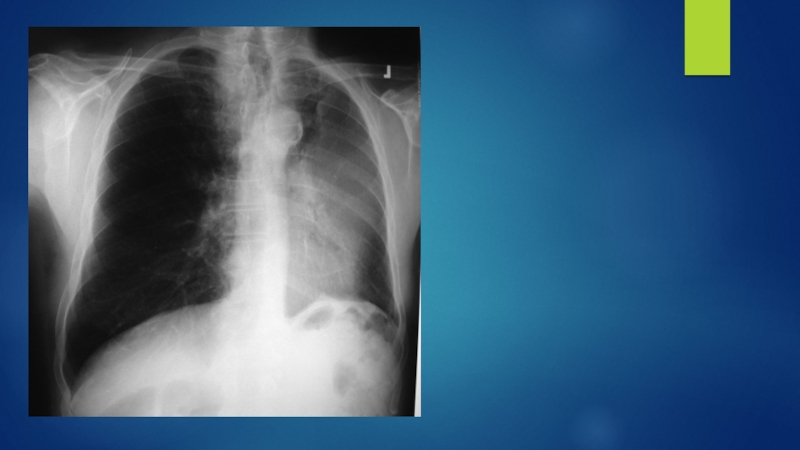

Рентгенография:

инфильтрат в легком

расширение средостенья

ателектаз

плевральный выпот

ДиагностикаСбор жалоб, анамнез.Данные объективного исследования.Рентгенография:инфильтрат в легкомрасширение средостеньяателектазплевральный выпотБронхоскопияЦитологическое исследование мокротыС целью определения степени распространенности процесса производят: